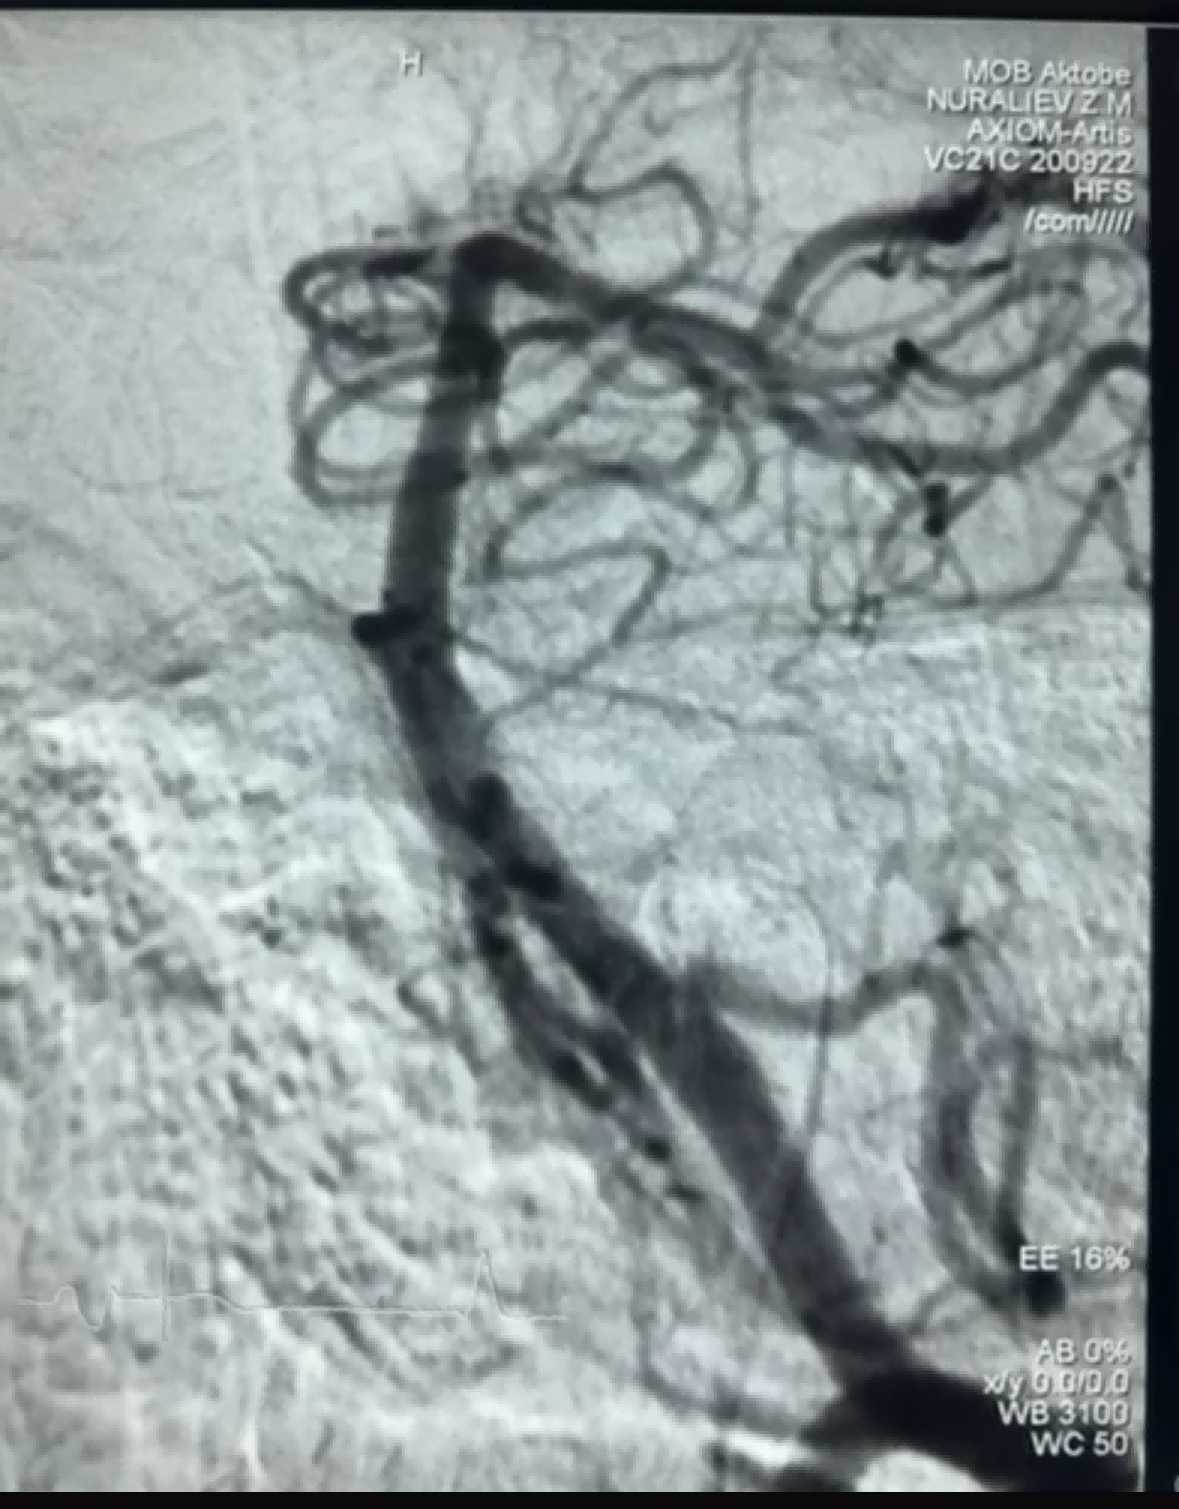

Tsis ntev los no, muaj kev vam meej thrombectomy rooj plaub uas siv Dredger Stent Retriever ntawm NeuroSafe Medical Co., Ltd. Lub Dredger Stent Retriever muaj ib tug tsis-invasive soft tip, uas zoo heev txo qhov kev pheej hmoo ntawm intimal kev puas tsuaj, thiab muaj ib tug tshwj xeeb-zoo li tus qhov. tsim uas ntes cov ntshav txhaws feem ntau los ntawm clamping qhov kev hloov pauv.